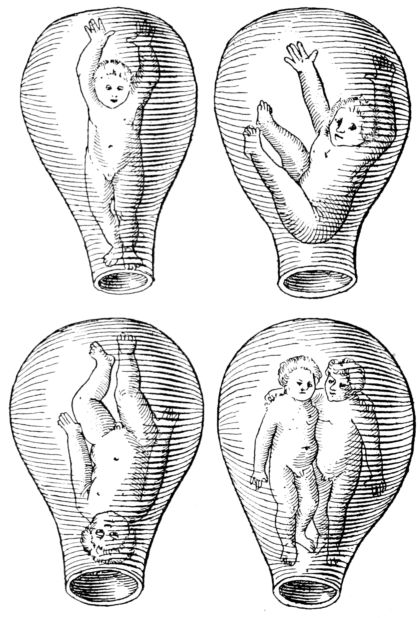

| 51. | Illustration from first text-book on obstetrics | 218 |